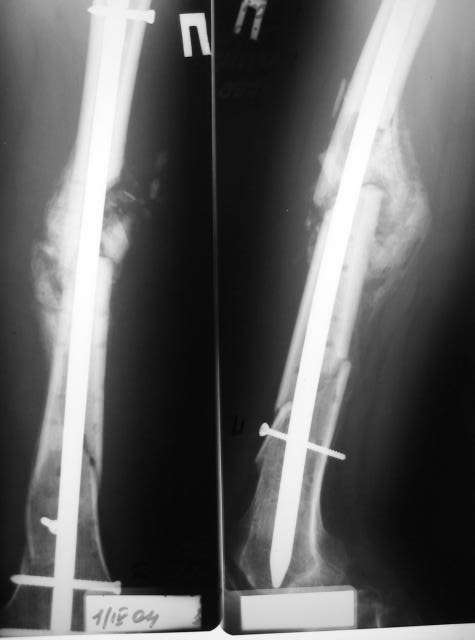

К нам обратились 24 01 04 родственники больного, с просьбой помочь больному. Мужчина 30 лет, 3 месяцаназад получил травму.

Диагноз: двойной оскольчатый перелом правого бедра в с/3 и н/3 со смещением, открытый оскольчатый перелом правой большеберцовой кости в с/3 со смещением двойной перелом малоберцовой кости. Оперирован проведена открытая репозиция, остеосинтез двумя пластинами бедренной кости, иммобилизация кокситной повязкой. На контрольных рентгенограммах от 21 01 04 имеется: несостоятельность остеосинтеза бедренной кости в в/3 выраженная угловая деформация; консолидирующийся перелом большеберцовой кости со смещением по длинне и выраженной вальгусной деформацией. Родственникам рекомендовали оперативное лечение. Больного доставят на осмотр 28.01.04, обдумываем способы лечения. Оперативное лечение планируем в два этапа, вначале на бедре, затем на голени. На бедре- удаляем верхнюю пластину, проводим остеотомию по линии верхнего перелома, проводим репозицию, остеосинтез пластиной с фиксацией верхнего, среднего и нижнего фрагментов.На голени-мнения разделились:- можно наложить аппарат внешней фиксации на голень, провести остеотомию б/берцовой кости в зоне перелома между проксимальным отломком и осколком, остеотомию малоберцовой кости, провести постепенную репозицию, тибиализацию (рисунок 3).-или провести остеотомию по линии перелома большеберцовой кости, репонировать и фиксировать пластиной. Новосибирская областьг Куйбышев ЦРБСергей Зырянов